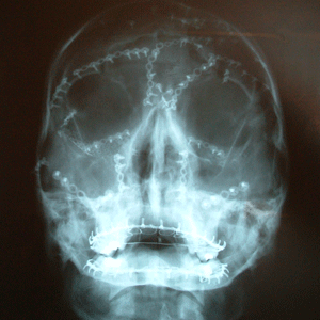

X-rays and post-op pictures

This shot shows some of the metal work around my mouth and

jaw. I had it wired up for over three months with arch bars to stabalise

my palette and wires to help my jaw set in place.